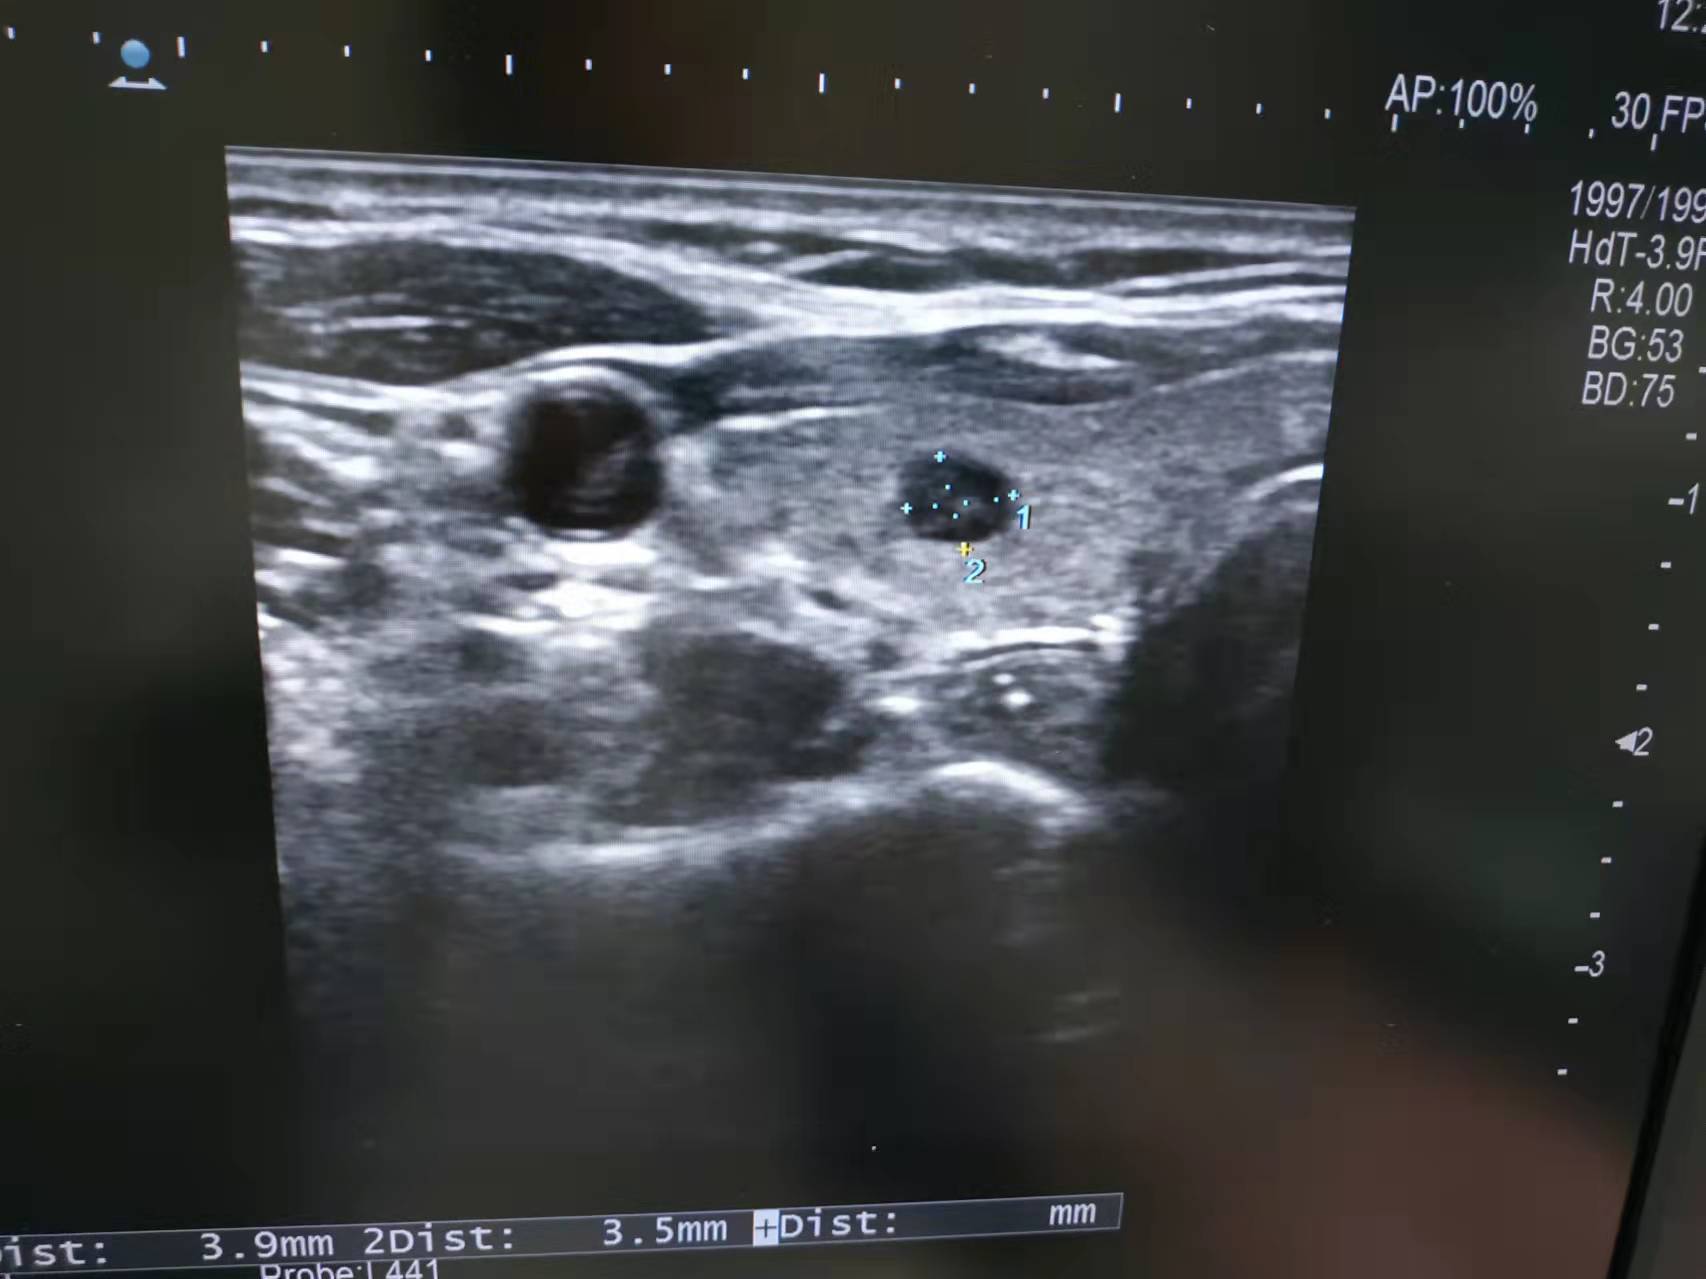

甲状腺超声图

经再次超声复核,医生建议小林在超声引导下做一个甲状腺细针穿刺活检术,通过穿刺取很少的甲状腺结节细胞就可以做病理及基因检查,来明确这个结节是良性的还是恶性的。